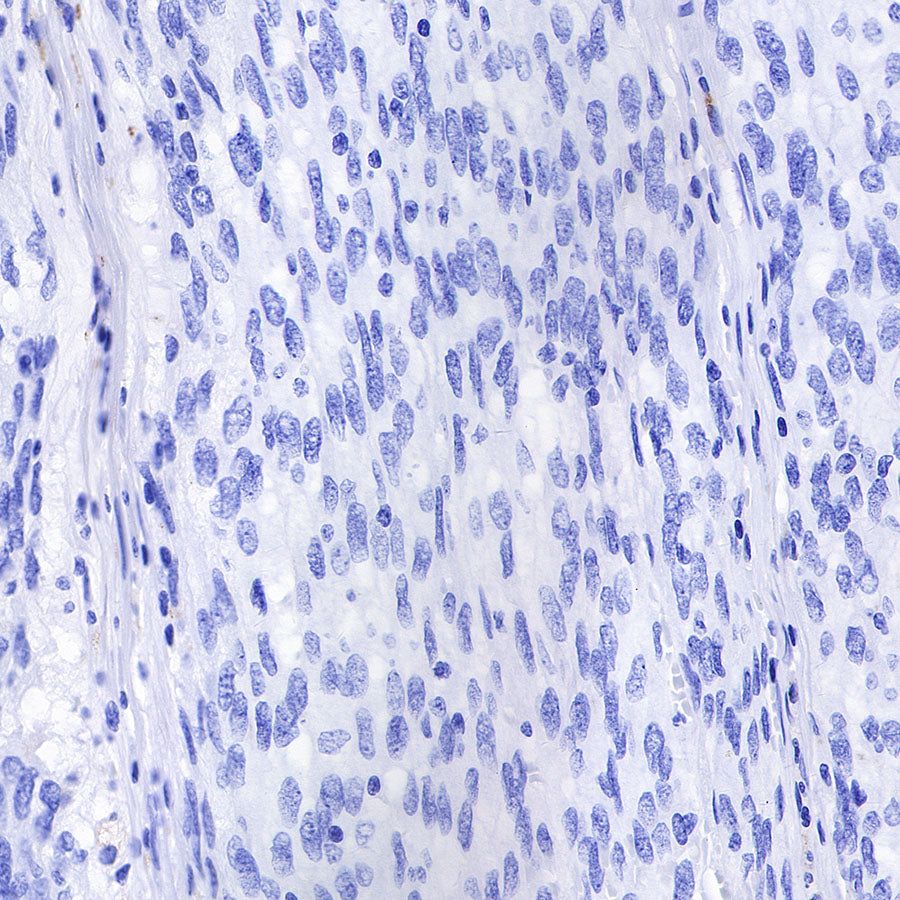

Negative control: IHC shows negative staining in paraffin-embedded human gastrointestinal stromal tumor. Anti-CD68 antibody was used at 1/1000 dilution, followed by a HRP Polymer for Mouse & Rabbit IgG (ready to use). Counterstained with hematoxylin. Heat mediated antigen retrieval with Tris/EDTA buffer pH9.0 was performed before commencing with IHC staining protocol.